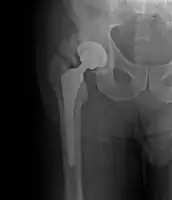

- Locations

- Hip most common - typically after ORIF (52% any grade, 19% Grade III-IV) or THA (43% any grade, 9% Grade III-IV)